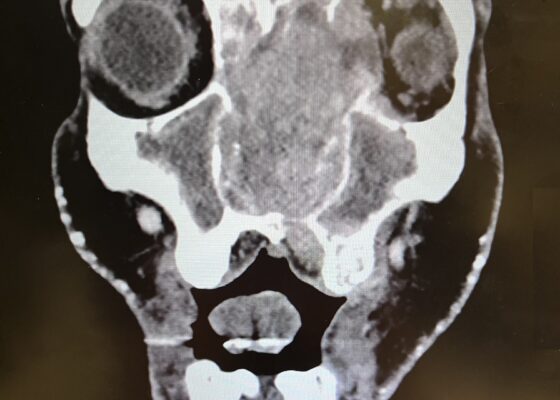

DOI: https://doi.org/10.5070/M5.52257Physical exam revealed a gross deformity of the left side of the face with soft tissue swelling with no overlying skin changes. The left eye was proptotic and completely immobile, with cranial nerve (CN) 3, 4, and 6 palsies. Additionally, a large obstructive mass was noted in the left naris with resultant rightward displacement of the nasal septum. Intraocular pressures (IOPs) were measured to be 6 mmHg in the right eye and 11 mmHg in the left eye.

Imaging, including maxillofacial and neck soft tissue CTs revealed a large, destructive, soft tissue mass centered in the nasal cavity with significant osseous destruction of the midface and skull base (red highlighted area). There was mild intracranial extension with the mass abutting or infiltrating the inferior frontal lobes (green highlighted area). The nasal cavity and nasopharynx were obstructed (orange highlighted area). The mass invaded the left orbit with associated left-sided proptosis, left globe deformity, and compressed the left optic nerve and the left optic chiasm (blue arrows).